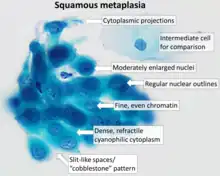

Pap tests commonly examine epithelial abnormalities, such as metaplasia, dysplasia, or borderline changes, all of which may be indicative of CIN. Nuclei will stain dark blue, squamous cells will stain green and keratinised cells will stain pink/ orange. Koilocytes may be observed where there is some dyskaryosis (of epithelium). The nucleus in koilocytes is typically irregular, indicating possible cause for concern; requiring further confirmatory screens and tests.